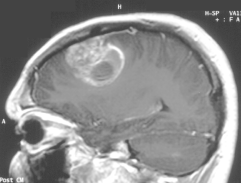

Scientists have found strong links between cell phone radiation exposure and occurrence of brain tumors

The World Health Organization has declared cell phone radiation a Class 2B possible carcinogen based on peer-reviewed science including epidemiological brain tumor studies.